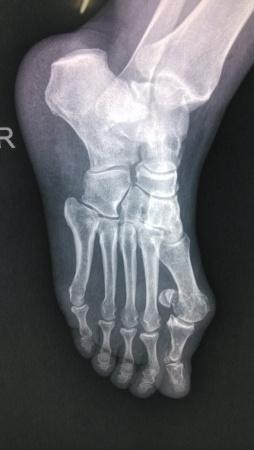

患者女性47岁,近期没有任何足外伤史(反复询问),于2个月前无诱因出现又足背部疼痛,走路时间长疼痛加重。请帮忙看下这个X光片有什么问题。 侧位看的不清楚

正位掌骨。

我和大家考虑一样,拇外翻肯定是有的。

拇趾外翻,足舟骨那个裂隙不是问题经常见,应该是投照较多问题,可以透视下变换**观察下

第一跖趾关节滑膜炎,第一跖骨头可见圆形低密度改变,不排除通风骨质改变。